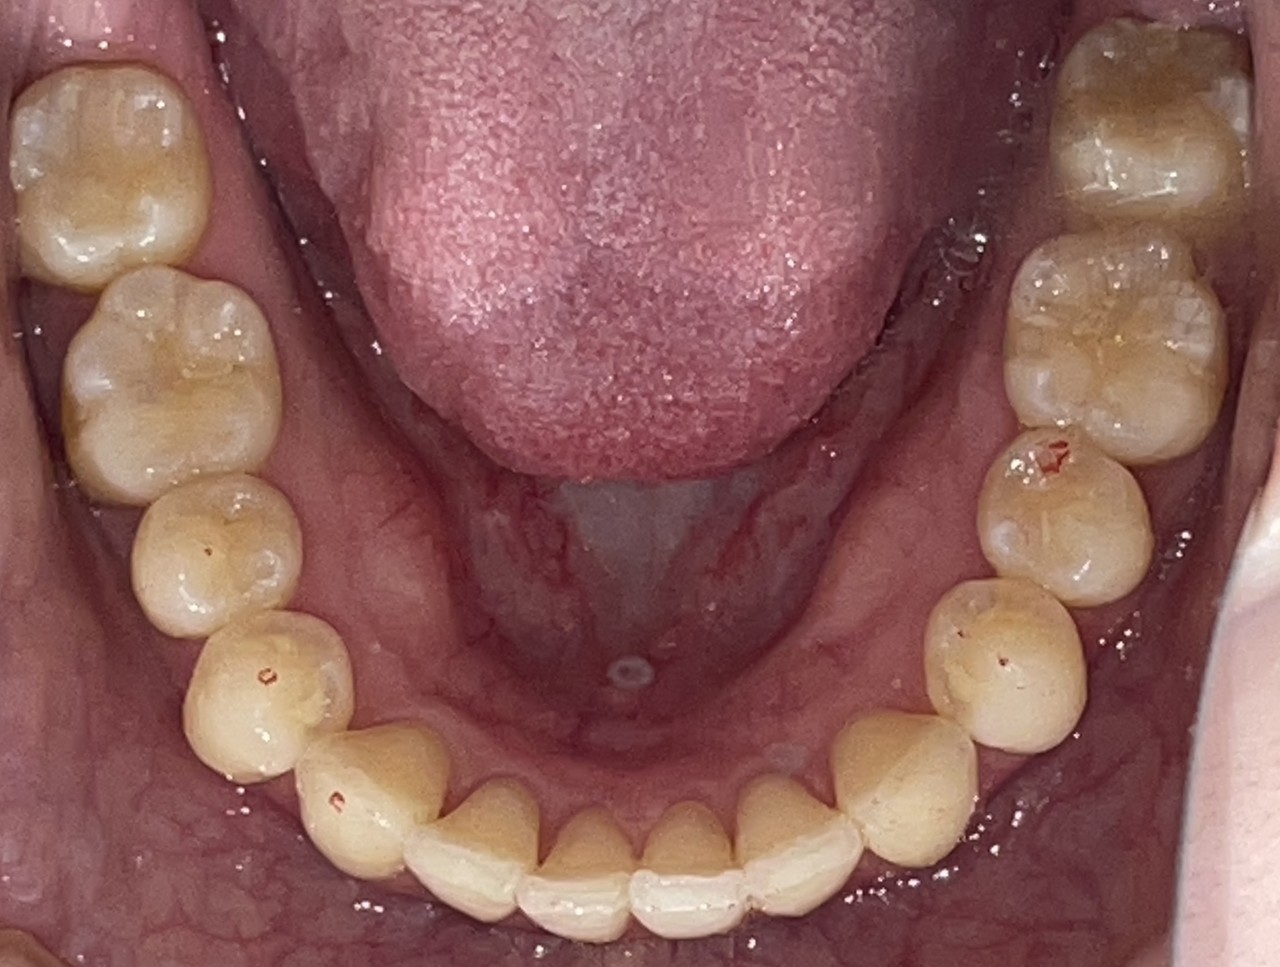

Before

After

矯正の種類 / invisalign GO

年齢・性別 / 10代男性

主訴  /  上顎叢生

治療期間 / 18ヶ月

費用 / 簡易検査 5,000円(税別) 精密検査 30,000円(税別)

両顎マウスピース 450,000円(税別) 両顎リテイナー料 40,000円(税別)

※マウスピース交換時別途調節料5,000円(税別)

副作用 / 口内炎・歯の移動に伴う痛み・知覚過敏 ※数日で収まる場合が多いです

リスク / 後戻り防止の為、夜のみマウスピースで保定を指示